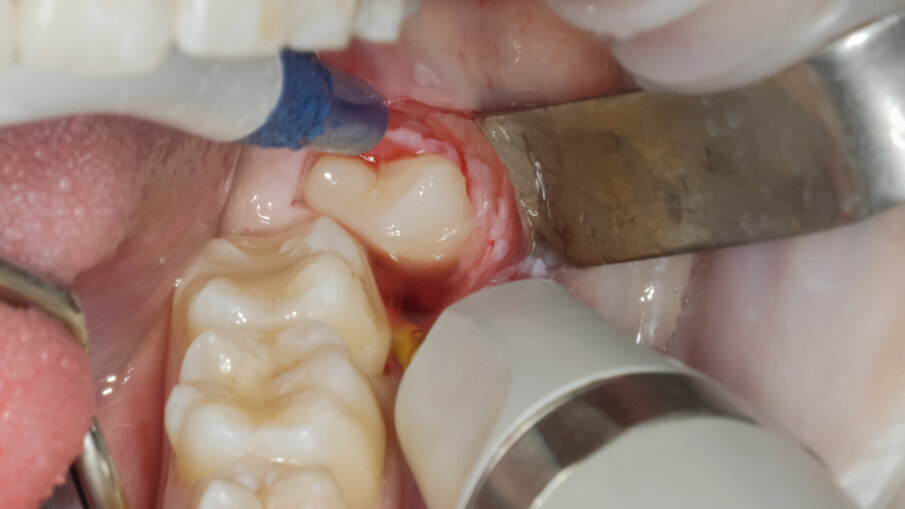

Si è presentata alla nostra osservazione la paziente A.M di 18 anni ASA 1 con disodontiasi di 38 e 48 lamentando fastidi localizzati all’area degli ottavi inferiori in fase finale di terapia ortodontica con allineatori trasparenti. Dall’ortopantomografia si poteva definire la classificazione di Pell e Gregory in classe II C e normoverso per quella di Winter (Fig 1). Vista la prossimità con il nervo alveolare inferiore, la incompleta formazione degli apici radicolari e la sintomatologia si è deciso insieme alla paziente di eseguire l’estrazione per ridurre i possibili rischi di danno neurologico dopo sottoscrizione del consenso informato. Previa anestesia tronculare della terza branca del V paio di sinistra con Carbocaina senza v.c. e plessica con Articaina 4% con v.c. 1:100000 si è proceduto all’incisione intrasulculare di 37 con scarico disto vestibolare. Lo scollamento del lembo mucoperiosteo è stato ottenuto mediante inserto PR1 al fine ottenere i vantaggi biologici come descritti da von See (Fig. 2).

L’ostectomia di accesso per evidenziare la corona è stata praticata mediante inserto SLO-H. Questo inserto nasce per il disegno della botola ossea nel rialzo di seno laterale, ma per la sua forma e il forte potere tagliente risulta molto efficace anche nella ostectomia peridentale (Figg. 3, 4). Mediante fresa a fessura in carburo di tungsteno montata su manipolo diritto sotto costante irrigazione di fisiologica sterile si è proceduto alla fase di odontotomia verticale in modo da separare la porzione corono radicolare mesiale da quella distale (Fig. 5).